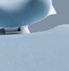

Figura 26. Caso clínico tratado mediante injerto óseo de bloque xenogénico (Bio-Graft® Geistlich Pharma). Continuación. A) Situación clínica tras 26 semanas de cicatrización desde el primer procedimiento. Vista vestibular. B) Situación clínica tras 26 semanas de cicatrización desde el primer procedimiento. Vista oclusal. C) Situación radiográfica tridimensional tras 26 semanas de cicatrización desde el primer procedimiento. D) Reentrada, segunda intervención quirúrgica para la colocación de implantes. Vista oclusal.

Figura 27. Caso clínico tratado mediante injerto óseo de bloque xenogénico (Bio-Graft® Geistlich Pharma). Continuación. A) Protocolo de fresado para la colocación de implantes en hueso reconstruido. B) Colocación de implantes (Straumann Tissue Level®) sin retirada de los tornillos de osteosíntesis. C) Retirada de los tornillos de osteosíntesis y colocación de pilares de cicatrización. D) Radiografía inmediata posoperatoria. E) Cicatrización 8 semanas después de la colocación de implantes. F) Carga protésica 8 semanas después de la colocación de implantes.